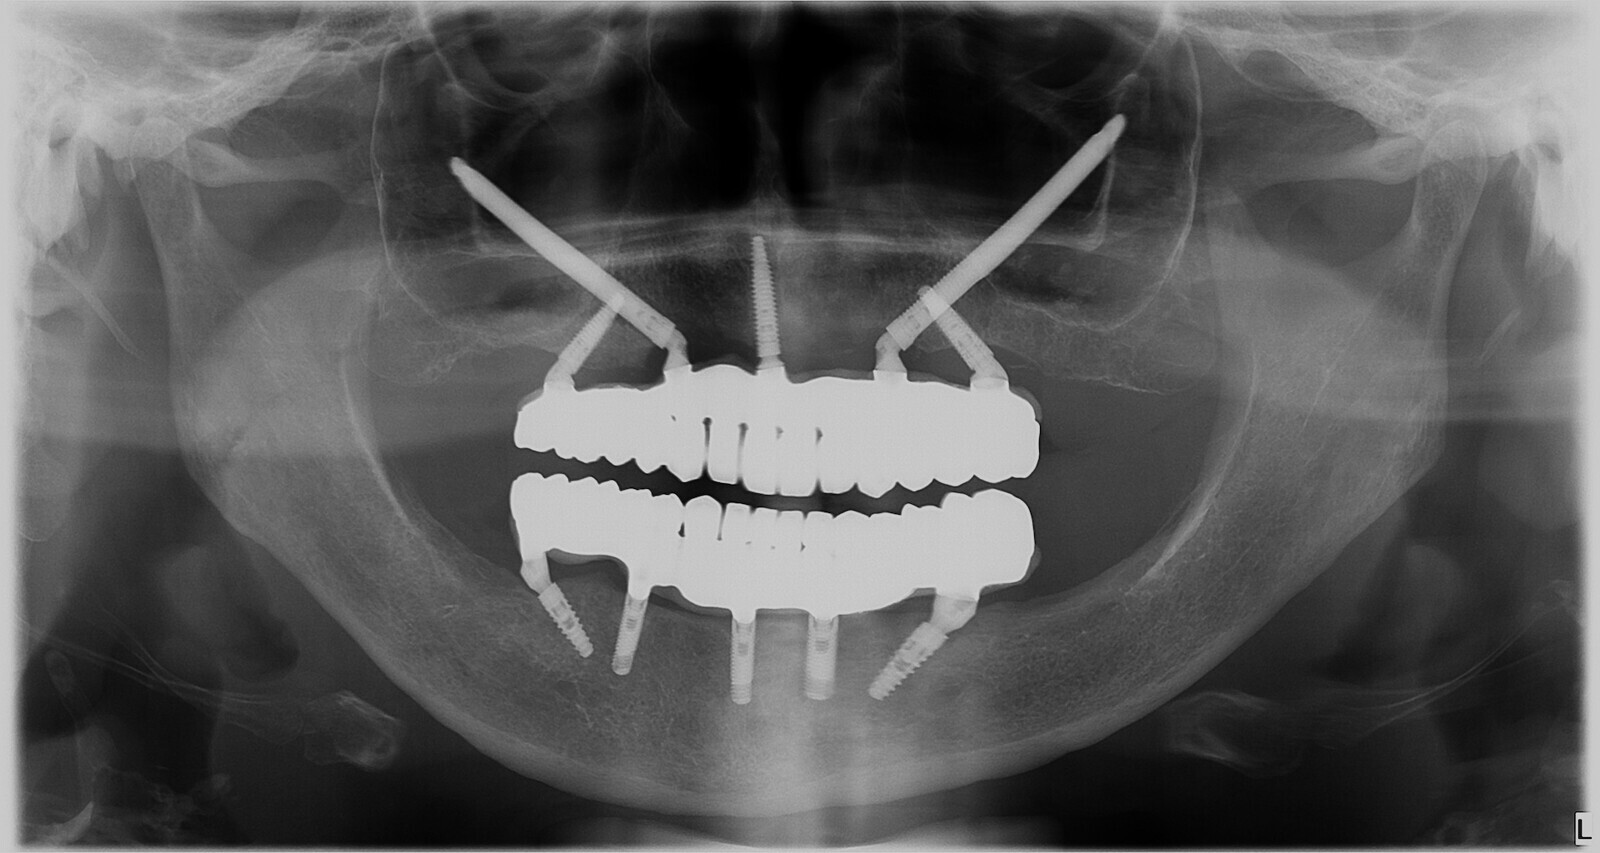

Aspecto radiográfico inicial y final y varios de los pasos realizados para la rehabilitación del maxilar con implantes cigomáticos de una paciente de edad avanzada.

Figura 1. Aspecto radiográfico inicial de la paciente de 72 años.

Figura 4. Radiografía panorámica después de la instalación definitiva de la prótesis.